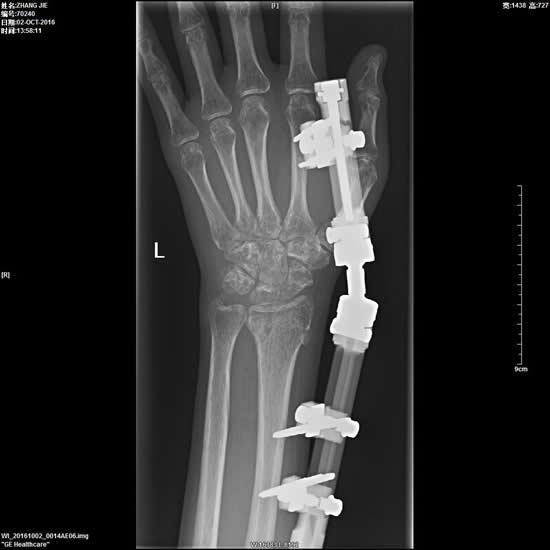

2、外固定架治疗四肢骨折。

6、四肢骨折的复位内固定术。